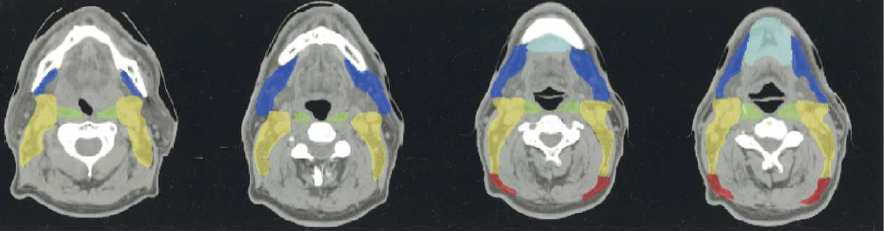

(a–l) Marked lymph nodes (LNs) with each LN group separated by color.

Light blue, submental LN (Ia);

dark blue, submandibular LN (Ib);

yellow, jugular LN (II, III, IV);

red, spinal accessory LN (V);

light green, retropharyngeal LN;

orange, parotid LN;

dark green, anterior jugular LN (VI);

pink, retroauricular/occiptal LN.